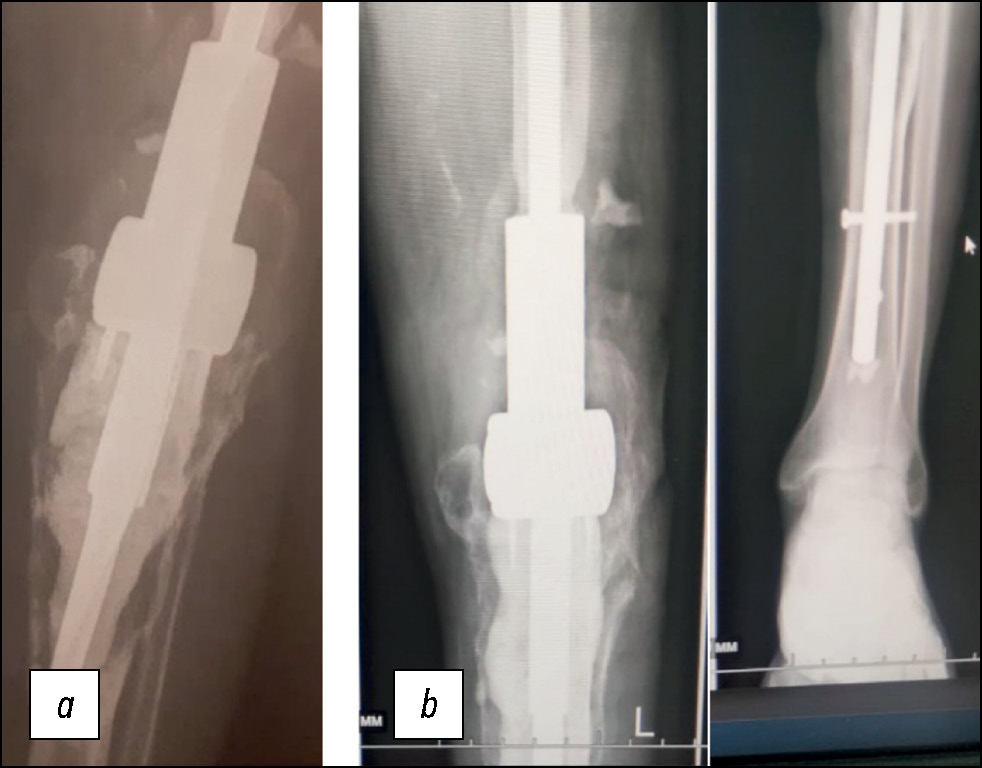

В 2003 г., спустя 13 лет после предыдущей операции, пациент упал на льду. На рентгенограммах выявлены смещение мыщелков трансплантата, их лизис, износ полиэтиленового вкладыша эндопротеза (рис. 4а).

Рис. 4. Рентгенограммы: a — до, b — после удаления межмыщелкового эндопротеза и имплантации эндопротеза коленного сустава Сиваша с удлинённой ножкой бедренного компонента.

Fig. 4. Radiographs: a — before, b — after removal of the intercondylar endoprosthesis and implantation of the endoprosthesis of the Sivash knee joint with an elongated leg of the femoral component.

Учитывая сложившуюся ситуацию, было принято решение удалить трансплантат и межмыщелковый эндопротез и имплантировать эндопротез коленного сустава Сиваша с удлинённой ножкой бедренного компонента. Данная конструкция относилась к связанным шарнирным эндопротезам.

06.05.2004 г., через 20 лет после имплантации межмыщелкового эндопротеза, пациенту выполнили операцию удаления эндопротеза и разрушенного трансплантата с замещением дефекта эндопротезом коленного сустава Сиваша с удлинённой ножкой бедренного компонента (рис. 4b). Большеберцовый компонент эндопротеза фиксировали в проксимальном отделе большеберцовой кости костным цементом. Послеоперационный период протекал без осложнений. Через 3 месяца после операции больной ходил с полной нагрузкой на оперированную конечность.

В 2006 г. была выполнена операция по замене повреждённого бедренного компонента эндопротеза на онкологический вариант с цементной фиксацией ножки в бедренной кости (рис. 5). Послеоперационный период протекал без осложнений. Девять лет пациент передвигался без дополнительных средств опоры. Боли не беспокоили.

Рис. 5. Рентгенограммы: a — до, b — после замены удлинённой ножки бедренного компонента эндопротеза Сиваша на её усиленный вариант.

Fig. 5. Radiographs: a — before, b — after replacing the elongated leg of the femoral component of the Sivash endoprosthesis with its reinforced version.